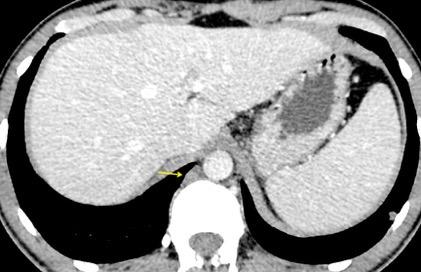

“Seudoquiste pancreático”

Seudoquiste pancreático

3 rasgos:

1. Conexión entre mediastino y lesión pancreática.

2. Derrame pleural

Matsusue E et al.Three cases of mediastinal pancreatic pseudocysts. Acta Radiol Open. 2016 .

3. Hallazgos de pancreatitis. Panda A et al. “Straddling Across Boundaries”. Thoracoabdominal Lesions: Spectrum and Pattern Approach.Curr Probl Diagn Radiol, 2015